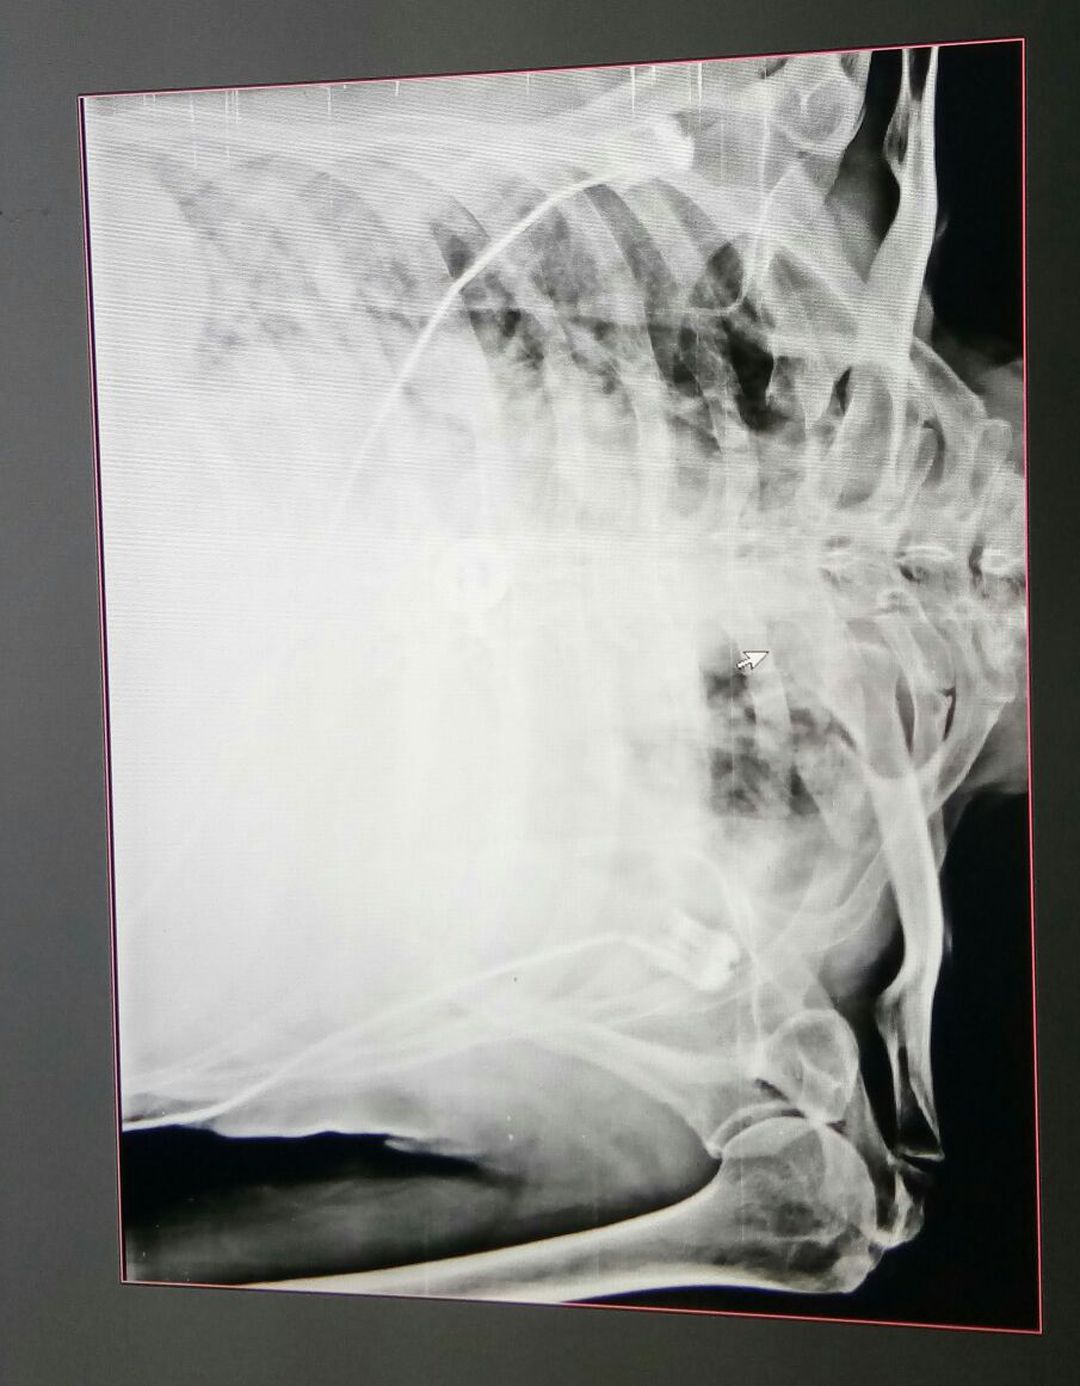

Pneumonia

Chestxray

Atlectasis

Covid 19